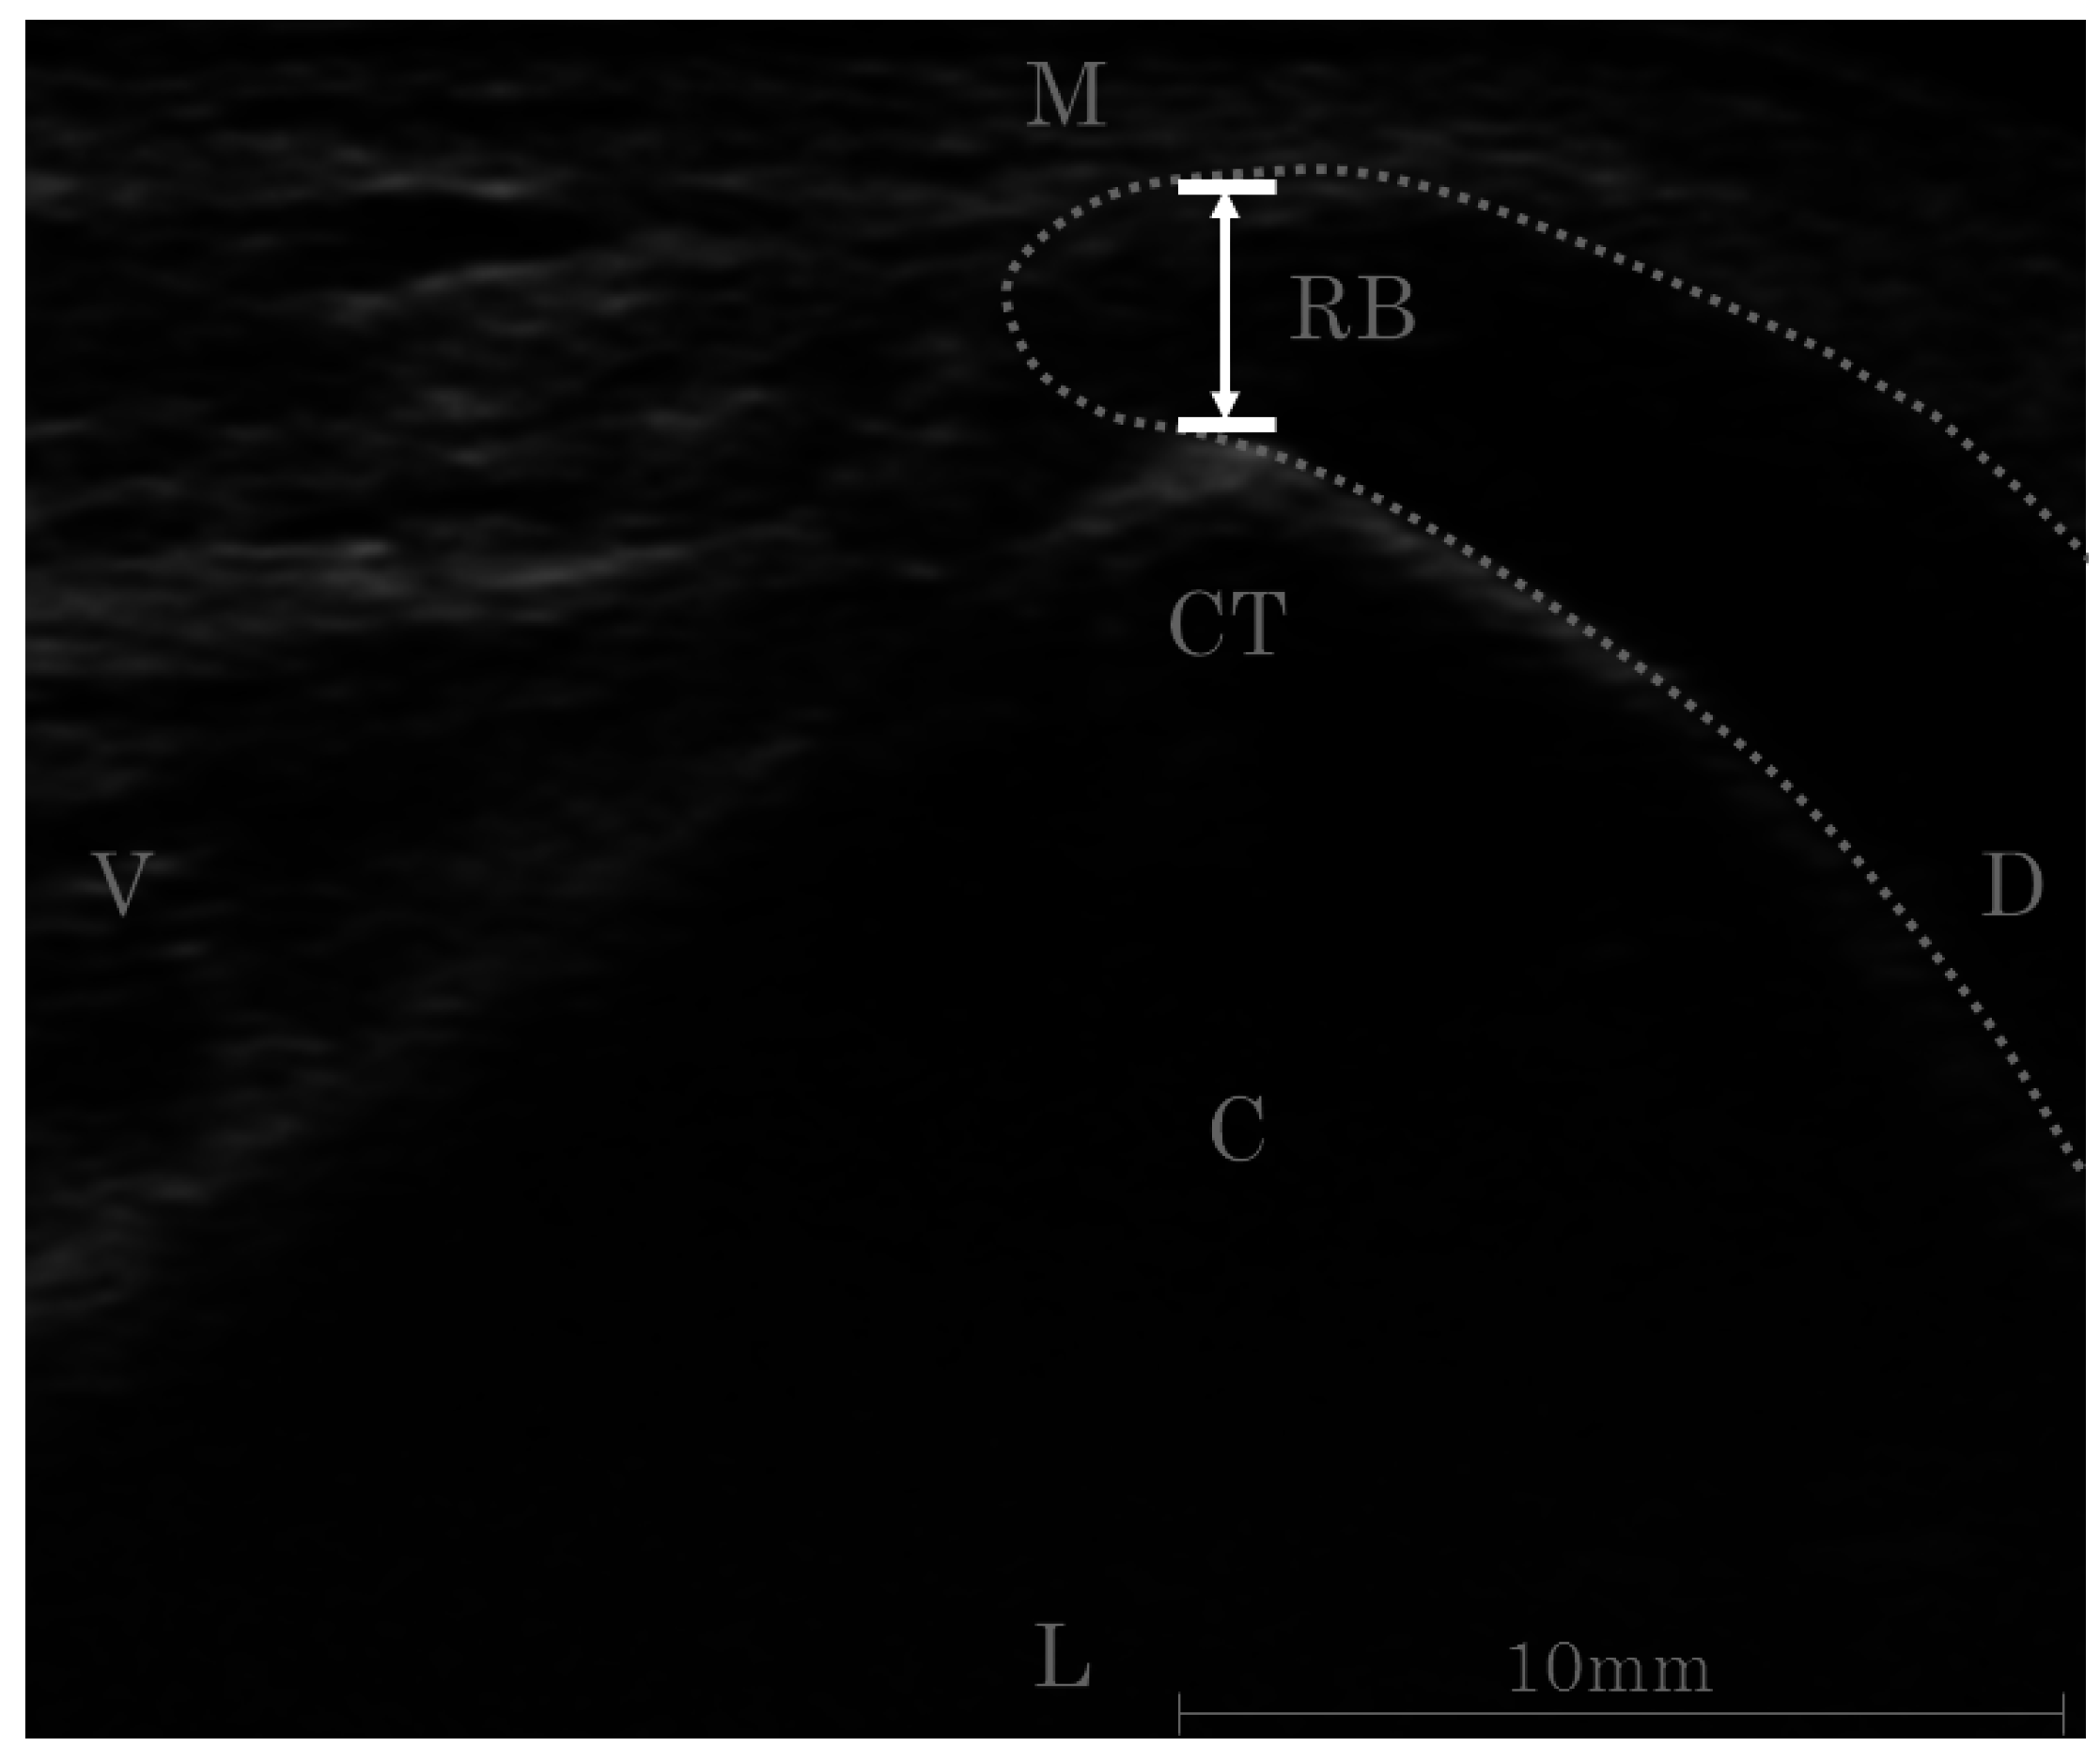

The thickness of RB was measured using an ultrasound imaging system (Prosound α-7, Hitachi, Japan) in three ankle positions (20° dorsiflexion, neutral, and 40° plantar flexion) with or without FHL contraction; all subjects were kneeling (90° hip flexion, 90° knee flexion) to relax the gastrocnemius (Figure 2). A 14 MHz linear array probe was used to measure the thickness of RB. The thickness of RB in the horizontal plane was defined as the distance between the posteromedial talar process and the calcaneal tuberosity (Figure 3). Before the study, the reliability of RB thickness measurement was calculated using the intraclass correlation coefficient, which ranged from 0.82 to 0.95 in each condition (ankle position and FHL contraction). The data were analyzed using the non-repeating two-way factorial analysis of variance and Tukey’s method for the post-hoc test. p ≤ 0.05 was considered as statistically significant.

Figure 3. Ultrasound measurement of the retrocalcaneal bursal thickness. Thickness of the retrocalcaneal bursa (defined as the shortest distance from the calcaneal tuberosity to the medial border of the bursal wall) is measured on the transverse plain. RB, retrocalcaneal bursa; C, calcaneus; CT, calcaneal tuberosity; D, dorsal; M, medial; L, lateral; V, ventral.